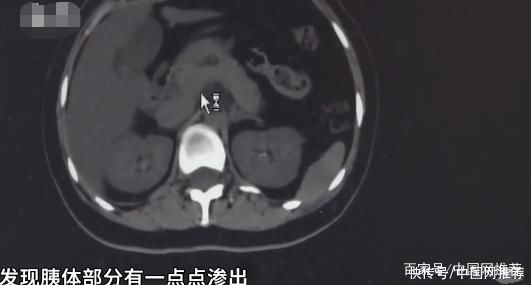

此外,林小姐的血酮、血白细胞、pH值、剩余碱、乳酸、肌钙蛋白等指标均有严重异常,随时可能危及生命。同时腹部CT显示,她的胰尾部局部膨隆,周围脂肪间隙模糊,有可能出现了胰腺炎。